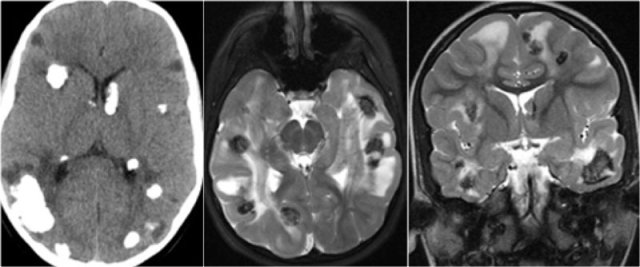

CT and MRI in a patient with Tuberous Sclerosis.

There are multiple cortcal and subependymal nodules.

The CT shows that most of the lesions are calcified.